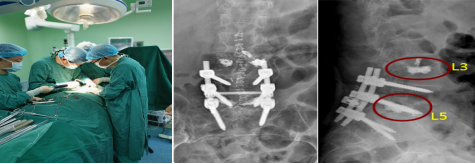

综合考虑患者病情,常规椎弓根螺钉置钉技术,固定失败率较高,难以取得良好的手术目的及效果。向患方交代相关问题后,患者希望手术的愿望强烈。经积极完善术前准备,在州人民医院与四川省人民医院搭建的“传帮带”平台上聘请了四川省人民医院俞阳副主任医师,于2020年9月9日在全麻下为患者进行了“腰3椎体成形术+经后路腰4-骶1椎椎管减压术+腰4/5、L5/S1神经根探查松解术+腰4/5、腰5/骶1椎间盘摘除、椎间植骨融合+骨水泥强化椎弓根钉内固定术”。手术在历时5小时30分钟后顺利结束。术后患者恢复好,局部疼痛明显缓解,术后需长时间防治骨质疏松治疗,目前患者腰腿疼情况已好转,生活质量得到明显的改善。